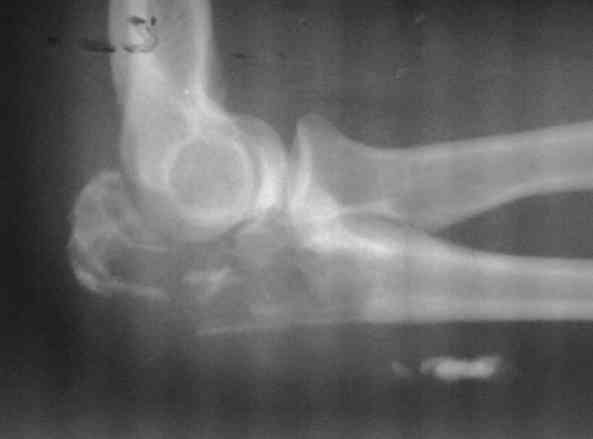

Женщина 39 лет, патологический перелом локтевого отростка,при гистологии ОБК. Помощь в определении тактики 1. артродез 2. протезирование ( возможно-ли, каким протезом (стандарт, онкологический) прогноз восстановление функции ) с ув. В.Машталов

А есть ли что сохранять? Сустав практически разрушен, суставная поверхность локтевой кости в результате перелома фрагментирована. Остался только плечелучевой сустав. О органосберегающей операции можно было говорить до перелома, когда еще была сохранена форма суставной части локтевой кости. Учитывая особенности локтевого сустава (высокая частота сгибательных послеоперационных контрактур, склонность к образованию параосификатов и т.п.) последующие артролизы, даже артроскопические (что вообще-то технически сложно), малоэффективны, а зачастую дают отрицательные результаты.

Поэтому, я бы предложил эндопротезирование сустава, или, как <позицию для отступления> - артродез сустава.